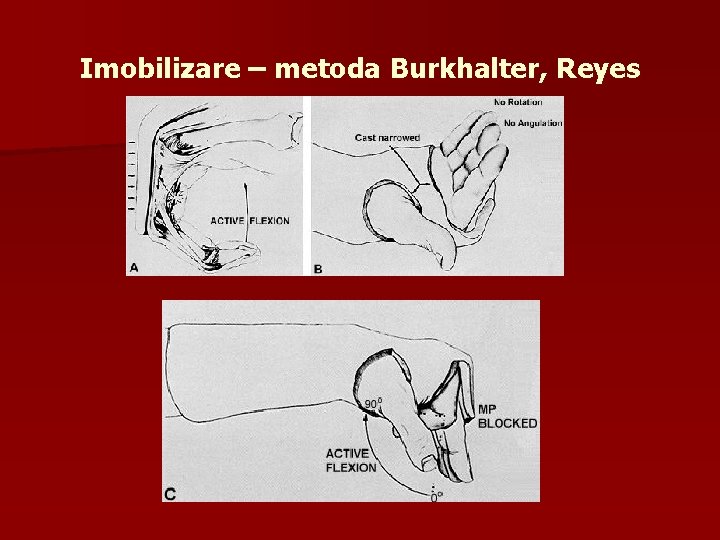

Imobilizare – metoda Burkhalter, Reyes